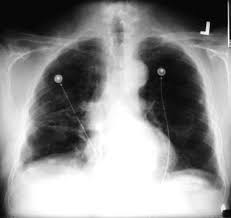

Pleural Plaques From Asbestos British Lung Foundation

Pleural Plaques From Asbestos British Lung Foundation from www.blf.org.uk